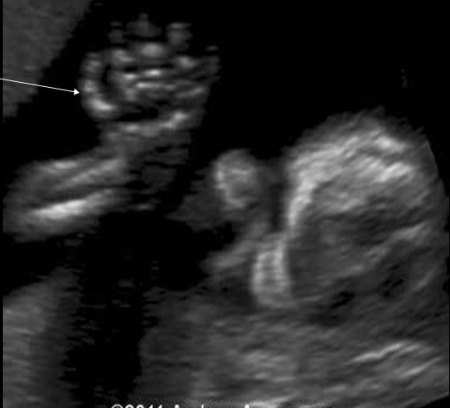

what pedal abn is assoc w/trisomy 13 + 18

a) talipes equinovarus

b) polydactyly

c) club foot

d) rocker bottom foot